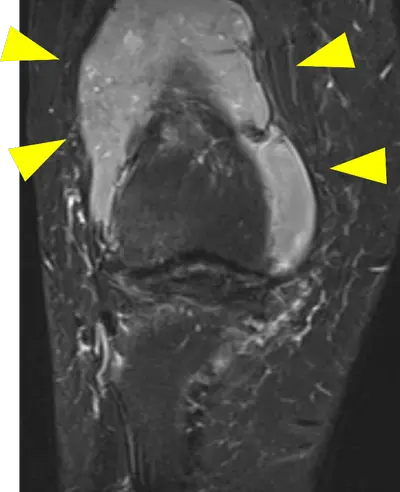

[50代 膝関節内軟部腫瘍] 膝関節をあけ直視下に腫瘍を辺縁切除施行。術後再発なく経過している。